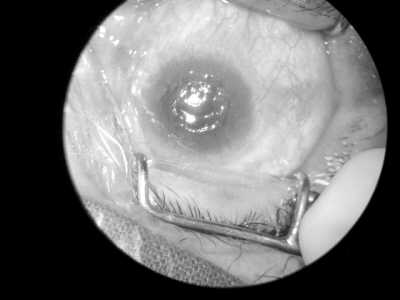

北京:首例飞秒板层角膜移植成功(见图二)

角膜感染易引发角膜盲,角膜移植是最有效方法。中国中医科学院眼科医院运用全飞秒微透镜摘除技术为3例患者进行了角膜移植,效果显著。

王俏 郝晓凤摄